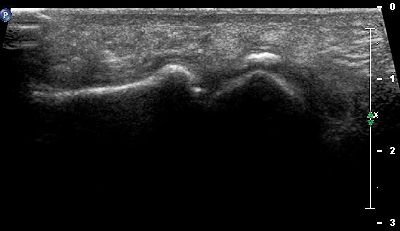

Testa metatarsale (img. 01) Modifiche anatomiche testa metatarsale 01

Testa metatarsale (img. 02) Modifiche anatomiche testa metatarsale 02

Testa metatarsale (img. 03) Modifiche anatomiche testa metatarsale 03